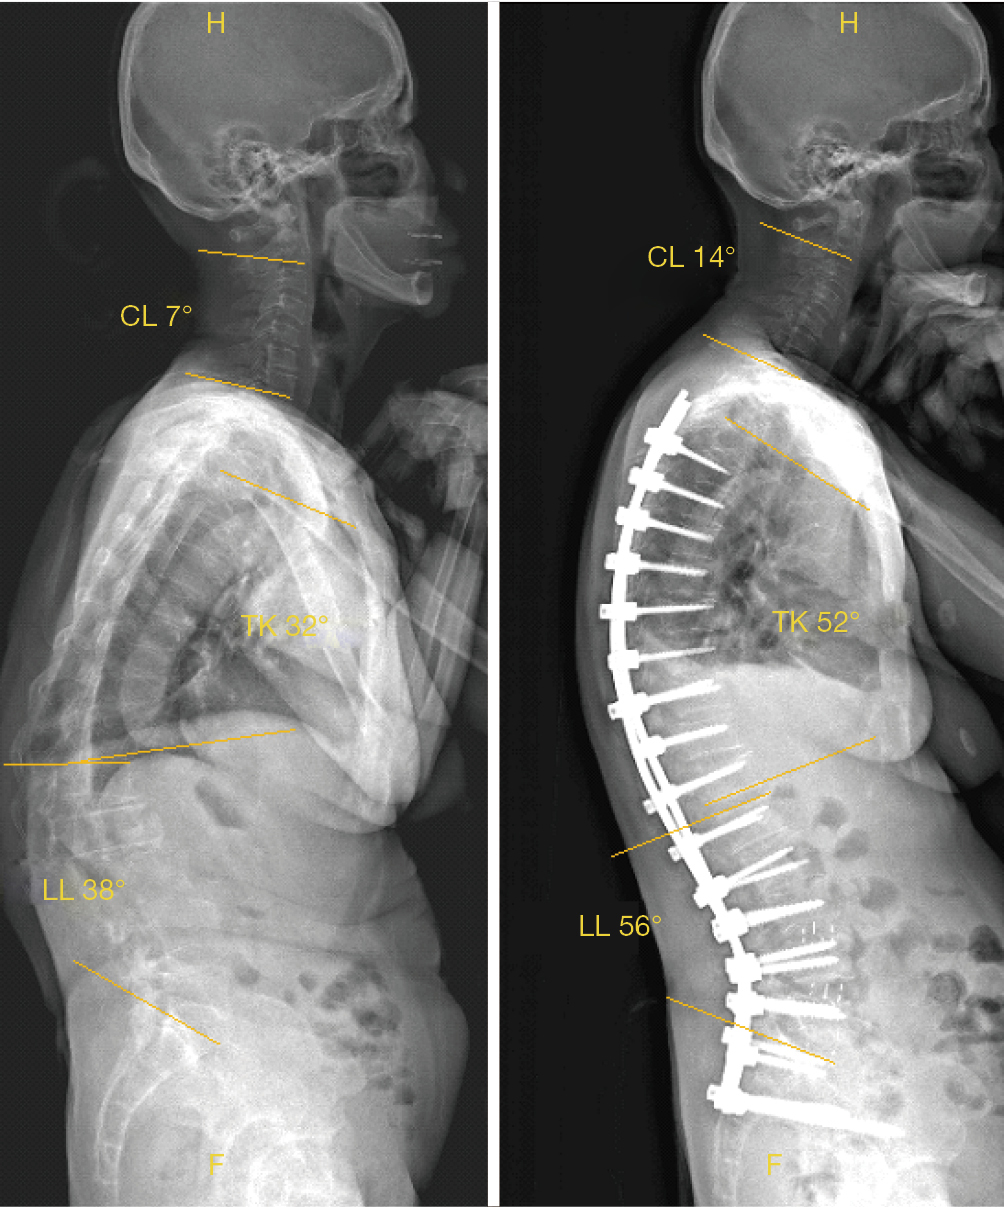

Roentgen Ray Reader Sagittal Balance and the Flat Back Syndrome Cervical Alignment And Sagittal Balance In patients with cervical spine pathologies, surgical consideration of alignment and balance is critical for obtaining optimal outcomes [ 1 ]. Cervical sagittal balance parameters, such as t1 slope, cervical sva (csva), and spine cranial angle (sca), were compared between the cervical. Studies on cervical sagittal alignment started from normative data, and. Adequate sagittal balance (sb) is essential to maintain. Cervical Alignment And Sagittal Balance.